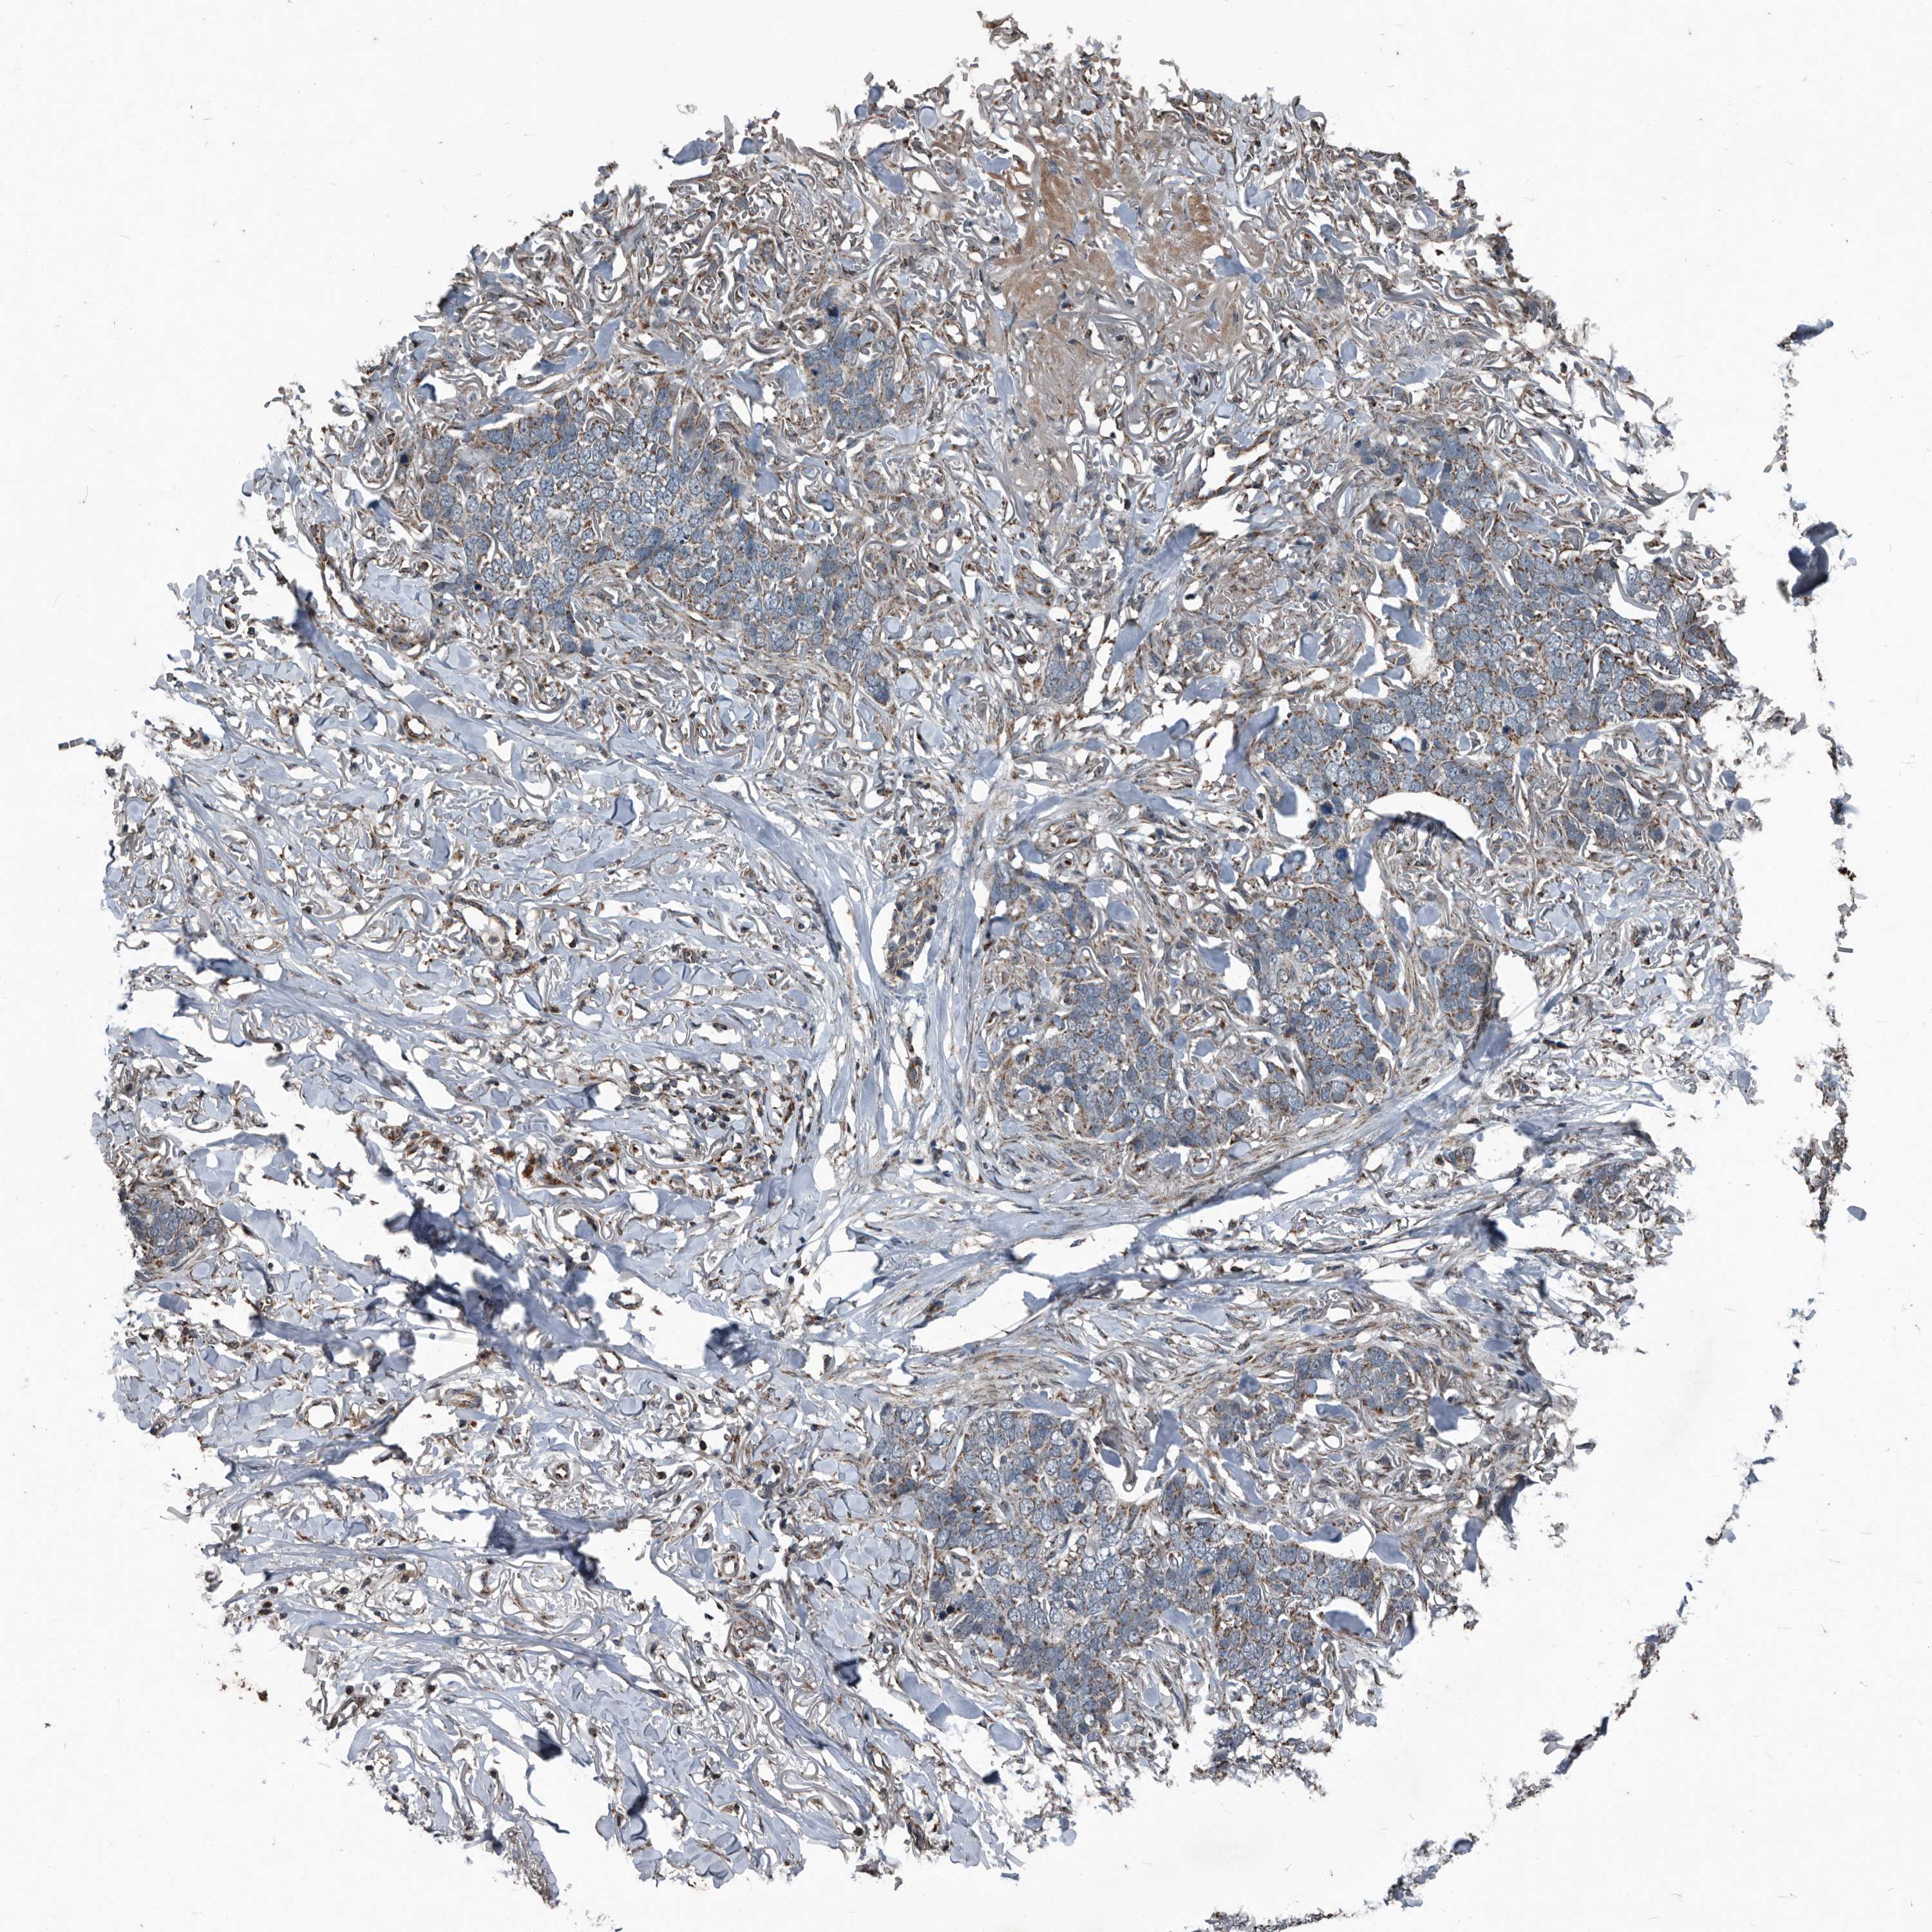

SKIN CANCER - Protein expressioni

A mouse-over function shows sample information and annotation data. Click on an image to view it in a full screen mode. Samples can be filtered based on level of antibody staining by selecting one or several of the following categories: high, medium, low and not detected. The assay and annotation is described here.

Antibody stainingi

Antibody staining in the annotated cell types in the current human tissue is reported as not detected, low, medium, or high, based on conventional immunohistochemistry profiling in selected tissues. This score is based on the combination of the staining intensity and fraction of stained cells.

Each image is clickable and will lead to virtual microscopy that enables deeper exploration of all samples and also displays staining intensity scores, fraction scores and subcellular localization as well as patient and tissue information for each sample.

Antibody HPA045174

Antibody CAB032821

Staining

High

Medium

Low

Not detected

Intensity

Strong

Moderate

Weak

Negative

Quantity

>75%

75%-25%

<25%

None

Location

Nuclear

Cytoplasmic/membranous

Cytoplasmic/membranous,nuclear

Basal cell carcinoma

BCC, high aggressive

Squamous cell carcinoma, NOS

Squamous cell carcinoma, metastatic, NOS